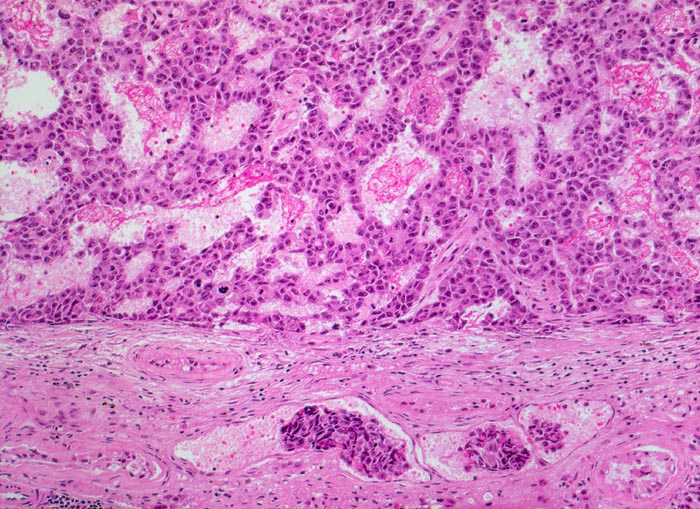

Histologisch bilden die Tumorzellen solide Zellplatten, Drüsen oder papilläre Strukturen mit Einblutungen und Nekrosen. Die Tumorzellen sind polygonal, kubisch oder zylindrisch, haben reichlich Zytoplasma und unscharfe Zellgrenzen. Die grossen Kerne haben grob verklumptes Chromatin und enthalten oft mehrere sehr grosse unregelmässige Nukleolen. Gefässeinbrüche und eine testikuläre intratubuläre Neoplasie sind in der Tumorumgebung häufig nachweisbar

• Polymorphe Tumorzellen bilden miteinander anastomosierende Stränge, solide Zellplatten, glanduläre und kribriforme Strukturen.

• Gefässeinbrüche in peritumoralen Gefässen.

• Tumorinfiltration des peritestikulären Fettgewebes.